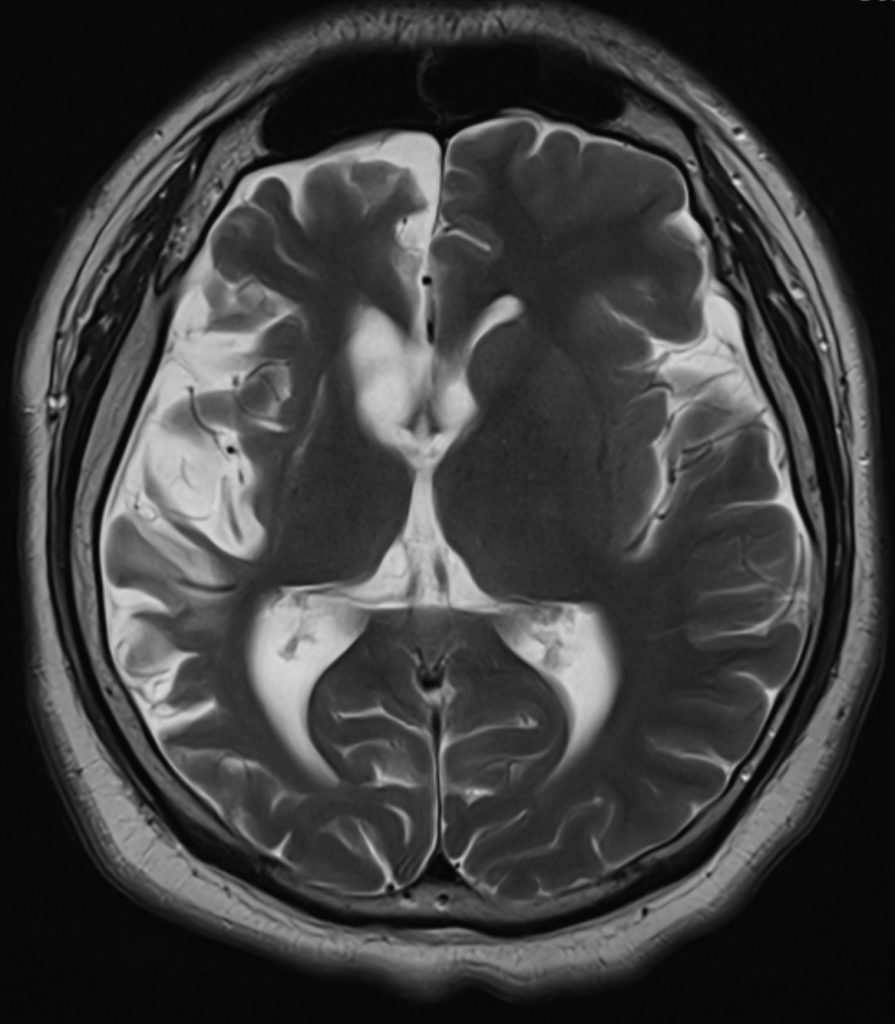

A plain CT brain revealed asymmetrical cerebral atrophy worse over the right hemisphere, predominantly affecting the frontal / temporal / insular regions, with proportional enlarged bilateral lateral and third ventricles. There were no gyral calcifications.

A contrast MRI brain illustrated a similar right hemisphere predominant atrophy, with mild T2W/ FLAIR hyperintense change over the atrophic right lentiform nucleus and right cerebral cortex. There were no leptomeningeal enhancement.